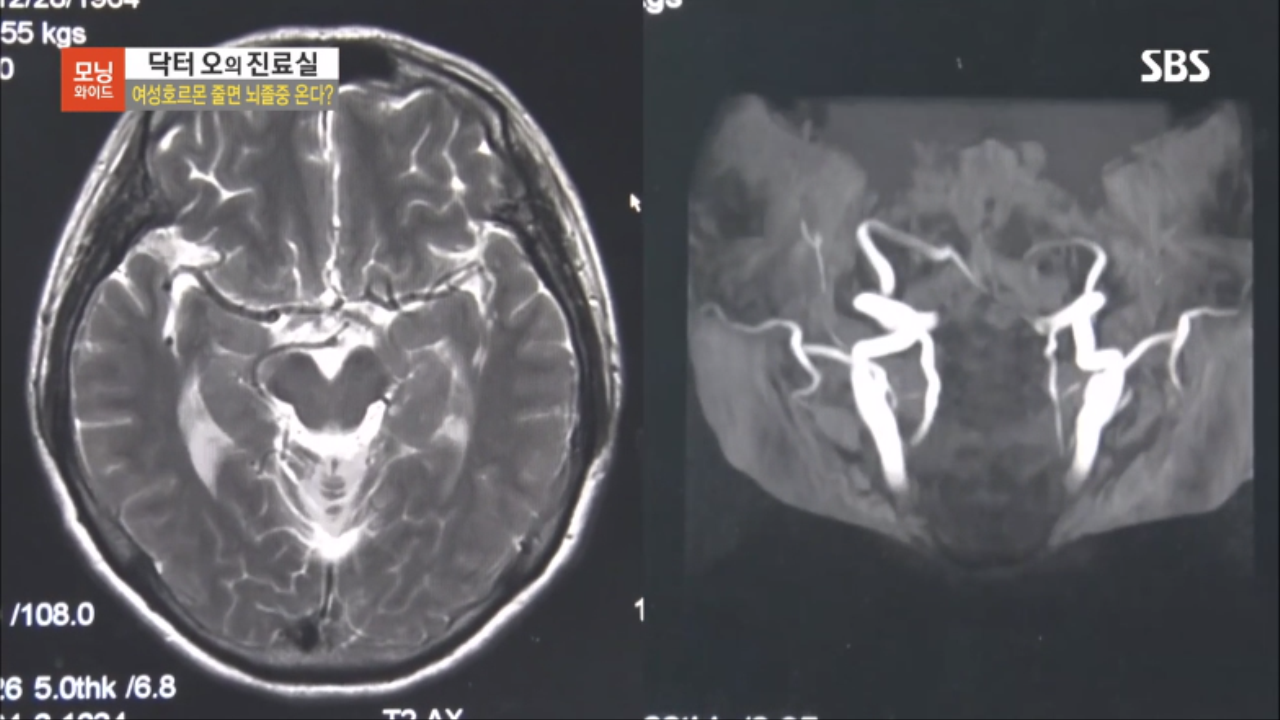

[SBS 모닝와이드] 여성호르몬 줄면 뇌졸중 온다?

중년여성의 갱년기 이후 뇌졸중 발병률 급증!

호르몬 변화에 의해 혈관이 약해지면 뇌혈관이

쉽게 막히거나 터질 수 있어 각별한 주의가 필요합니다.